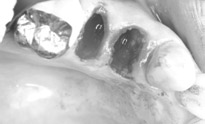

切開をせずインプラントを埋入します。 |

ソケットリフトもおこないました。 |